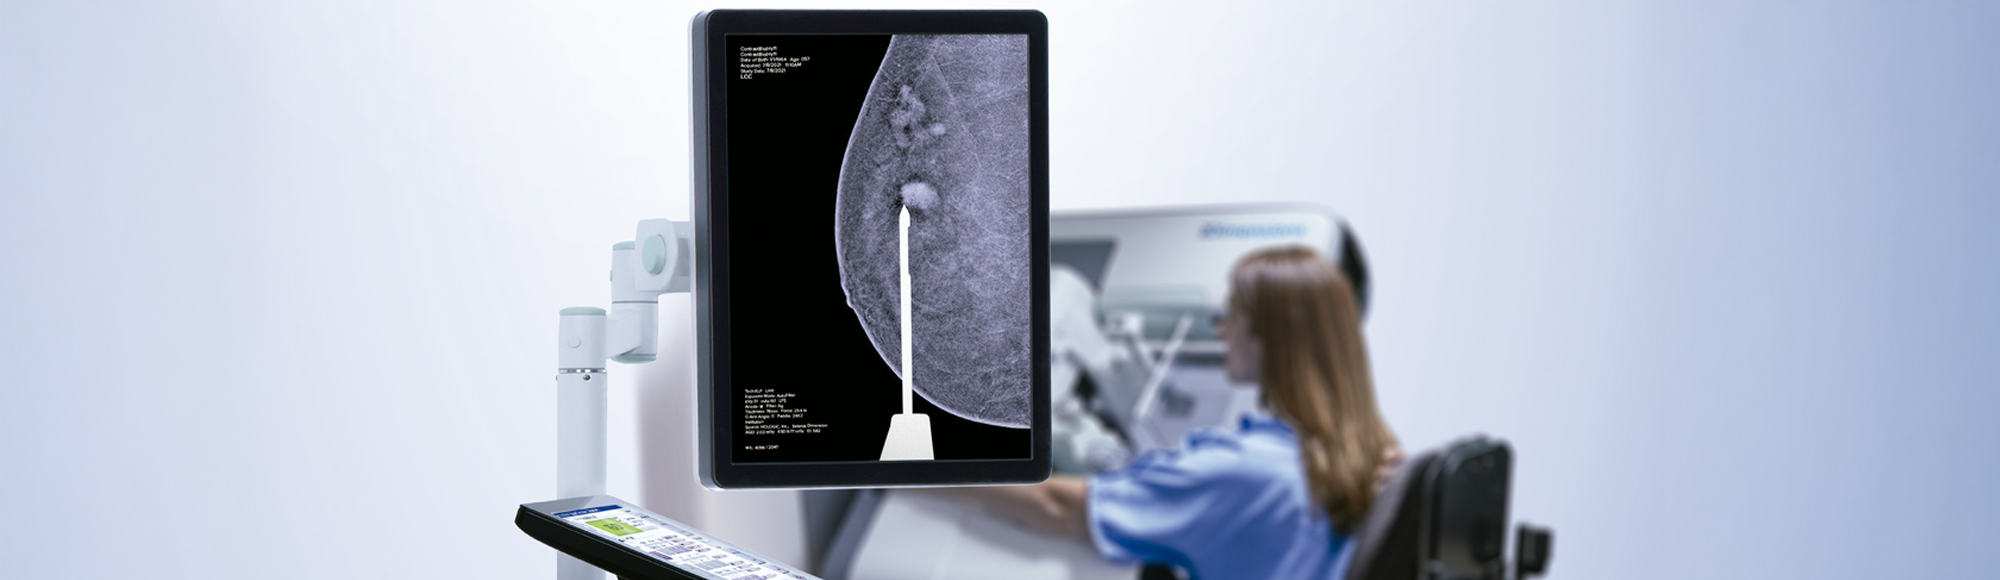

Diseñado desde cero para integrarse con los sistemas Selenia® Dimensions® y 3Dimensions™, el software de biopsia Affirm Contrast de Hologic permite a los médicos seleccionar y adquirir muestras de tejido en lesiones identificadas mediante mamografía con contraste (CEM).

El software permite la selección y adquisición de muestras de tejido en lesiones identificadas en CEM donde no se puede encontrar una correlación mediante tomosíntesis o ultrasonido, ofreciendo una alternativa a la biopsia guiada por resonancia magnética.

Con la potente cartera de mamografías y biopsias con contraste de Hologic, que incluye el sistema de biopsia Affirm Upright, el software de mamografía con contraste I-View® 2.0 y el software de biopsia con contraste Affirm, la empresa ofrece soluciones para guiar con confianza el camino clínico desde el cribado hasta el diagnóstico y la biopsia.